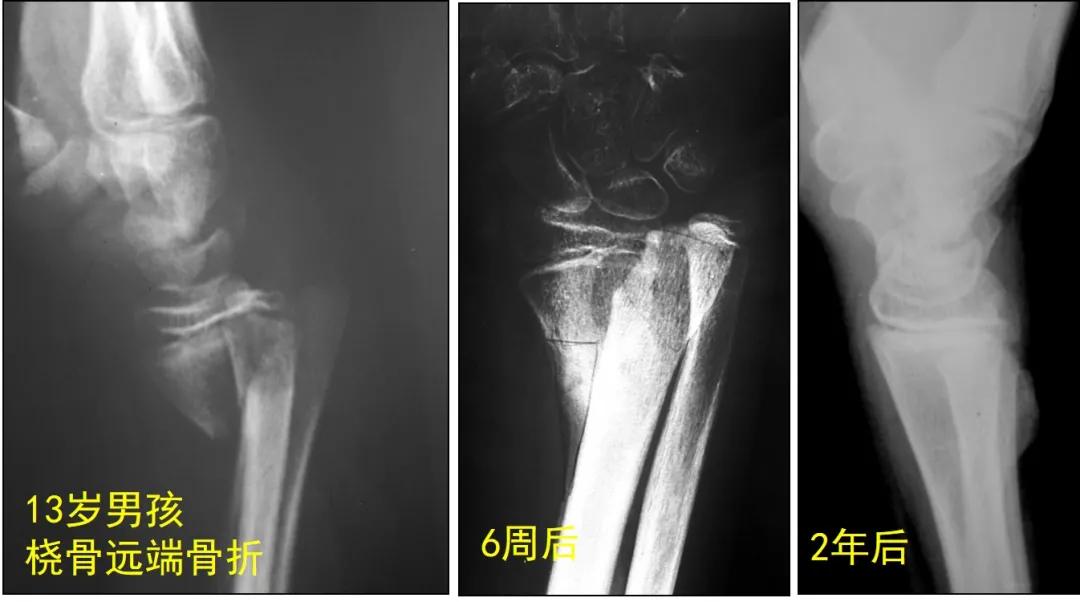

老师: 下面两个病例,分别是9岁4个月男孩的前臂中段骨折,保守治疗后3个月骨折对位、愈合良好。另外一个12岁男孩,早期外院保守治疗,三周时骨折再移位,于我院再次整复后恢复满意。

像下面这个10岁孩子,前臂远端骨折手术后8年,桡骨远端骺板早闭出现严重腕部畸形。所以,需要警惕,儿童“骺板”其实是把双刃剑,保护好了才能利于治疗,一定不能损伤它。